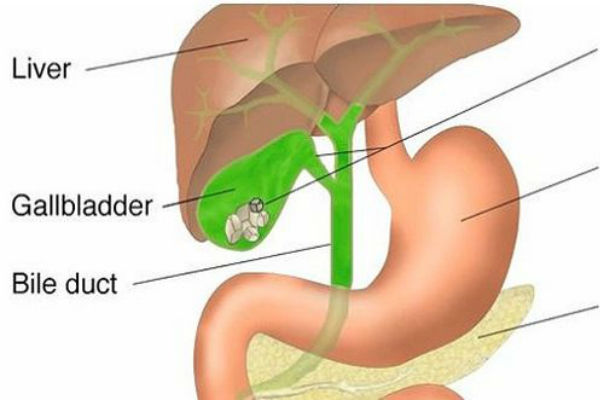

184.9KZdravljeNaznake pijeska u žuči 80 posto ljudi ne zna prepoznati

U organizmu žuč vrši funkciju cijepanja (emugliranja) masti. Ako se žuč slabo odvaja, ne dolazi do emugliranja. Stoga se vitamini rastvorljivi u...